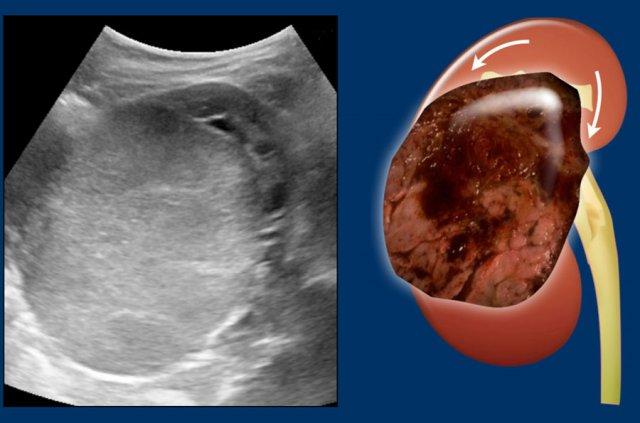

Dấu hiệu móng vuốt

Dấu hiệu này trong các khối u thận có giá trị trong việc xác định khối u xuất phát từ thận, thay vì chỉ nằm kề cận thận và làm biến dạng đường viền thận.

Hình ảnh

U Wilms bên trái ở bé gái một tuổi.

Phần thận còn lại trải dài bao quanh khối u, tạo thành “dấu hiệu móng vuốt”.